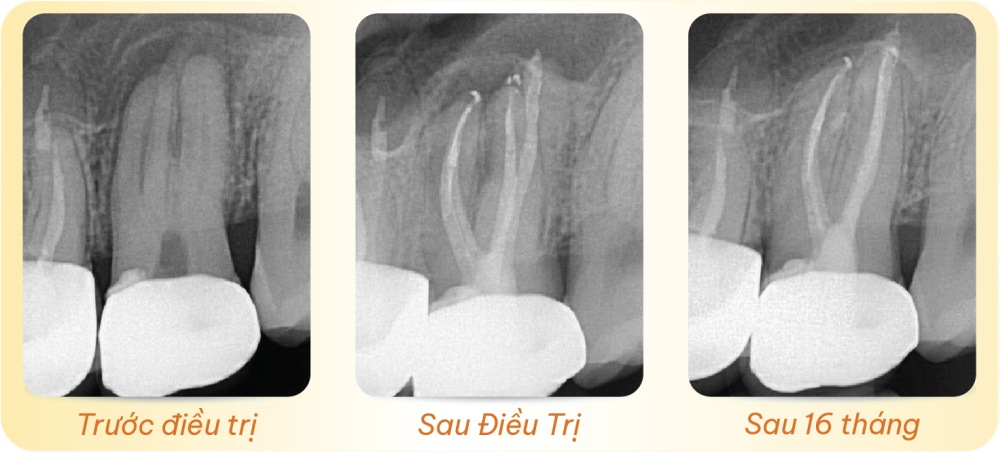

Trước điều trị – Sau Điều Trị – Sau 16 tháng